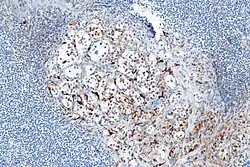

- Alrededor del 40% de los carcinoides tienen una dispersión de células sustentaculares, que se tiñen positivamente para S-100 .[6]